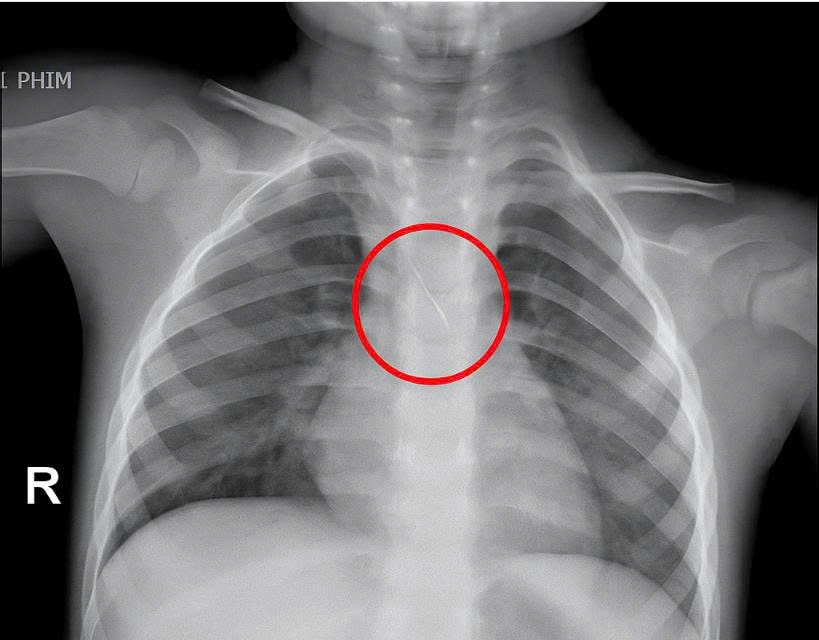

Trước đó, bé nhập viện trong tình trạng ho nhiều, ho sặc. Qua thăm khám và chụp phim, các bác sĩ xác định bé bị sặc kim chọc tủy dài khoảng 22mm, vị trí mắc tại góc carina, nơi chia đôi khí quản. Đây được đánh giá là ca cấp cứu nguy hiểm.

Bệnh viện kích hoạt hội chẩn liên khoa và quyết định tiến hành nội soi phế quản cấp cứu. Dị vật được phát hiện với một đầu nhọn cắm vào đoạn dưới khí quản, đầu còn lại nằm trong phế quản gốc trái.